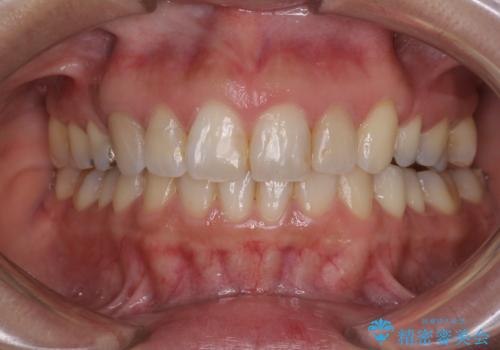

インビザラインにて抜歯矯正を行うと、高頻度で奥歯が咬み合わなくなります。

抜歯スペースが閉じてからも咬みにくさ改善のためマウスピース矯正を継続するため、治療期間は長期化します。